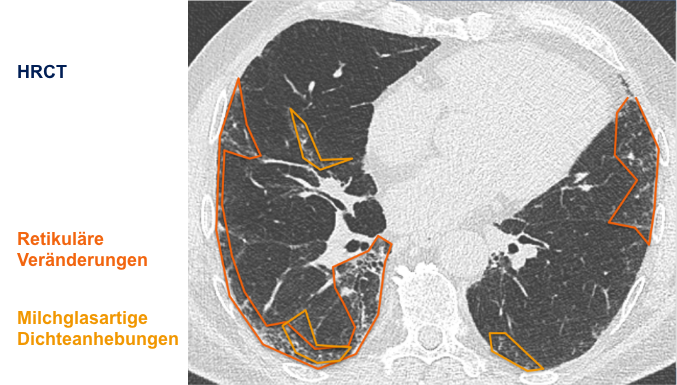

Der behandelnde Arzt hat sich für eine hochauflösende Computertomographie

(HRCT) des Thorax entschieden und folgende klinische Befundung erhoben:

Befundung des HRCT-Scans:

- Retikuläre Veränderungen

- Milchglasartige Dichteanhebungen

- Traktionsbronchiektasen

- Nicht vorhanden: Honigwabenmuster

CT: Computertomographie | HRCT: hochauflösende Computertomographie